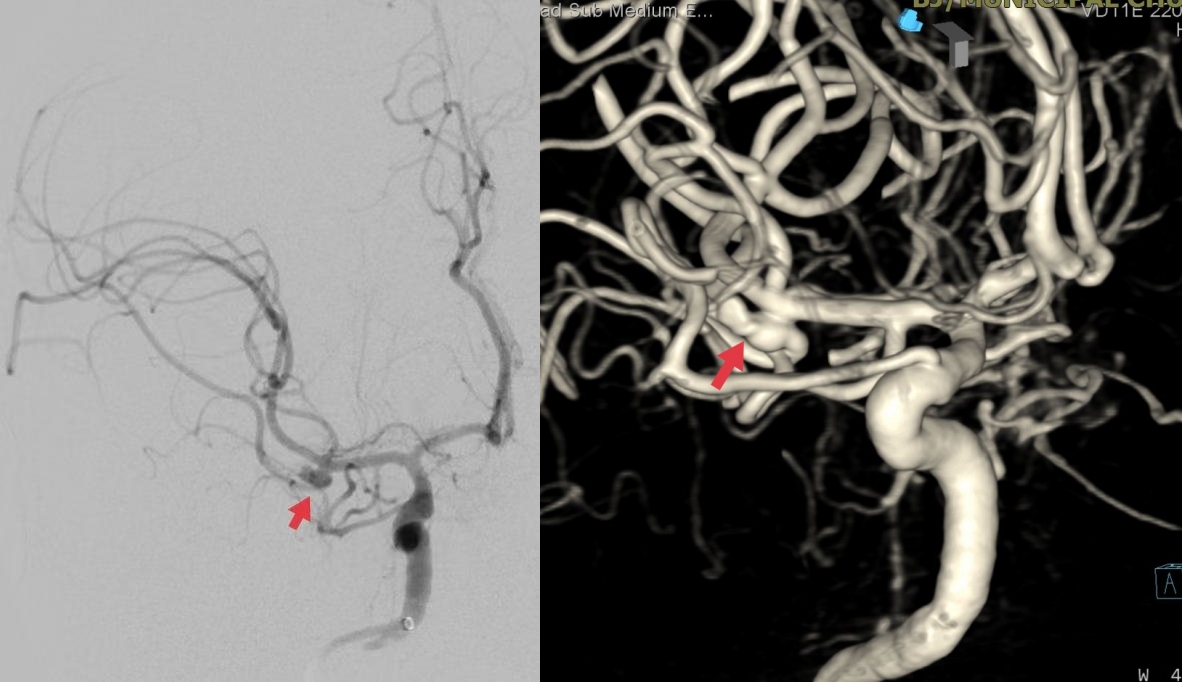

脑血管造影显示右侧大脑中动脉M1段分叉不规则动脉瘤,累及下干,角度刁钻。神经外科副主任医师刘磊决定采用单纯弹簧圈栓塞动脉瘤,避免因支架植入后需口服抗血小板药物进而影响后续的有创手术。经过2小时的手术,动脉瘤达到了致密栓塞,不定时炸弹拆除了,载瘤动脉各分支血流通畅。

脑血管造影显示右侧大脑动脉M1段分叉部不规则动脉瘤